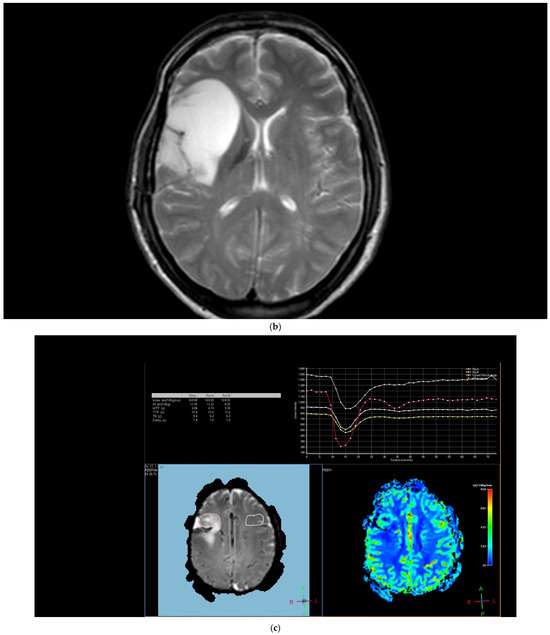

Figure 2. Brain magnetic resonance imaging (MRI) of a 67-year-old male with small-cell lung carcinoma revealed (a) peripherally enhanced right periventricular mass on post-contrast axial T1-weighted image and (b) hyperperfusion with a rCBV of 2.4 in perfusion-weighted imaging. Pink ROI is from metastatic nodule and white ROI is from contralateral parenchyma.